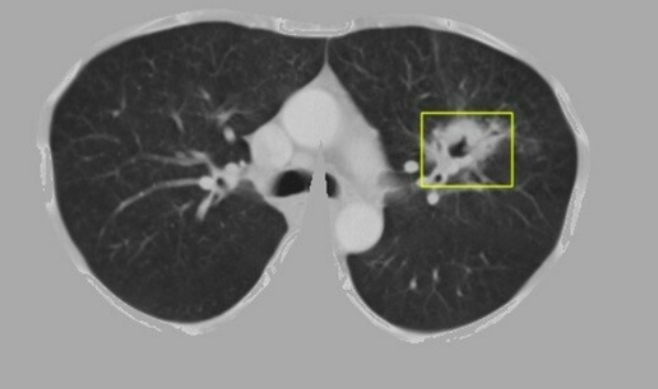

Khối u phổi được hệ thống định vị trong 5-10 giây.

Thông qua thuật toán, hệ thống có khả năng phát hiện vị trí, kích thước khối u phổi trên ảnh chụp cắt lớp, phân loại thành công khối u là lành tính hay ác tính. Hệ thống cũng khoanh vùng sớm điểm tổn thương nghi vấn trên ảnh để các bác sĩ có thể tập trung, nâng cao chất lượng chẩn đoán. Dựa vào tiêu chí đánh giá của ngành y tế, cả độ nhạy và độ đặc hiệu, hệ thống đều đạt trên 96%.